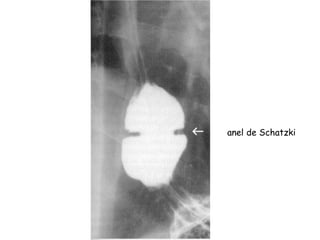

-Membrana esofágica inferior – anel de Schatzki

(sintomas se diâmetro < 13 mm);

anel de Schatzki